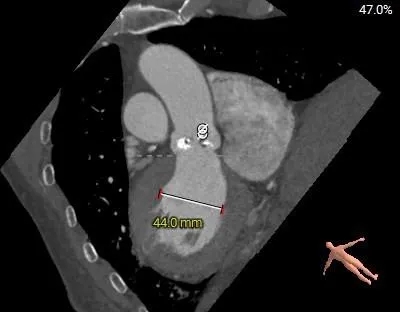

术前CT分析

Annulus

25.8mm

LVOT

瓣环水平夹角

52°

STJ 27.0mm

高21.0mm

AAO

31.6mm

L-29.9mm

R-30.0mm

N-31.6mm

-

三叶瓣,瓣叶增厚并钙化

直筒型LVOT,窦部空间不大

水平夹角52°,非横位心

瓣上 2mm

24.7mm

瓣上 4mm

25.5mm

瓣上 6mm

瓣上 8mm

24.0mm

瓣上 10mm

23.3mm

瓣上 12mm

22.3mm